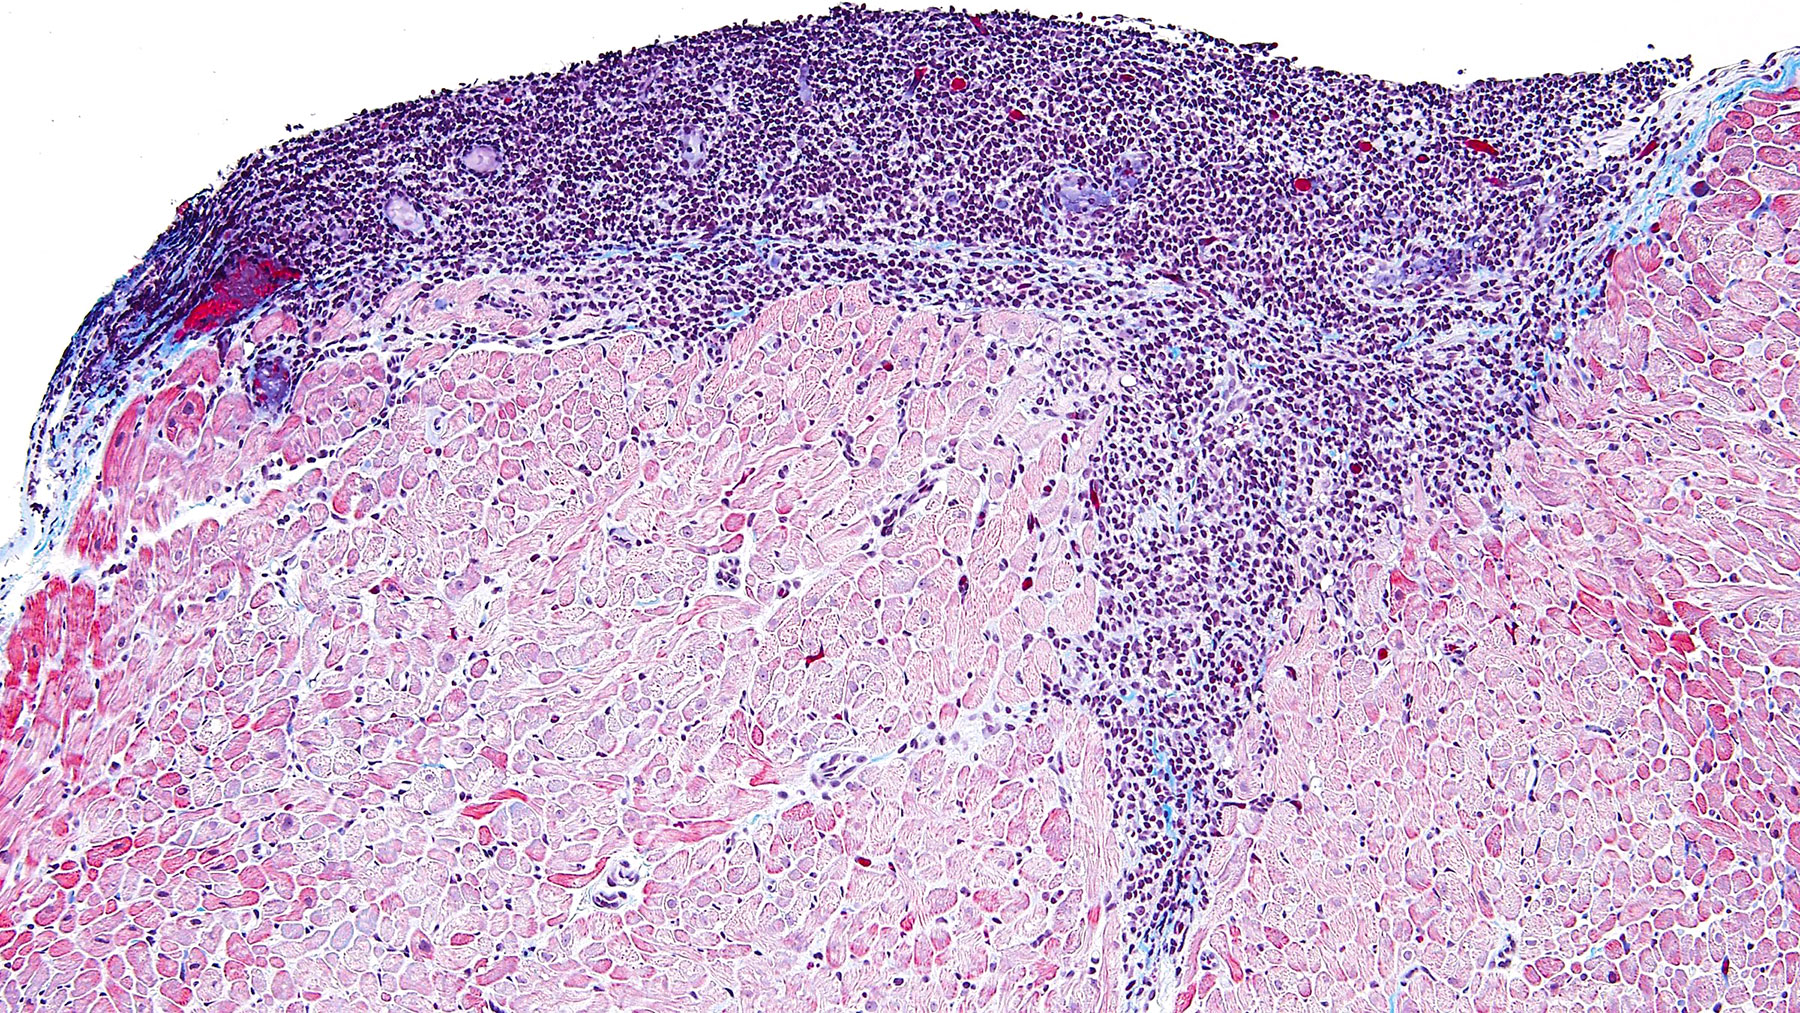

Figure D. CD21 (40x)

Histology: Figure A shows endocardium with a large focus of mononuclear inflammatory infiltrate spreading deeper between the myocardial fibers: this infiltrate shows focal myocyte encroachment and includes some plasma cells and a central capillary vessel. CD4, CD8 and CD20 are all positive (Figure E, F and B). CD21 is also positive which is a strong indicator of quilty effect. (Figures C and D). Trichrome staining shows no significant fibrosis (Figure G)